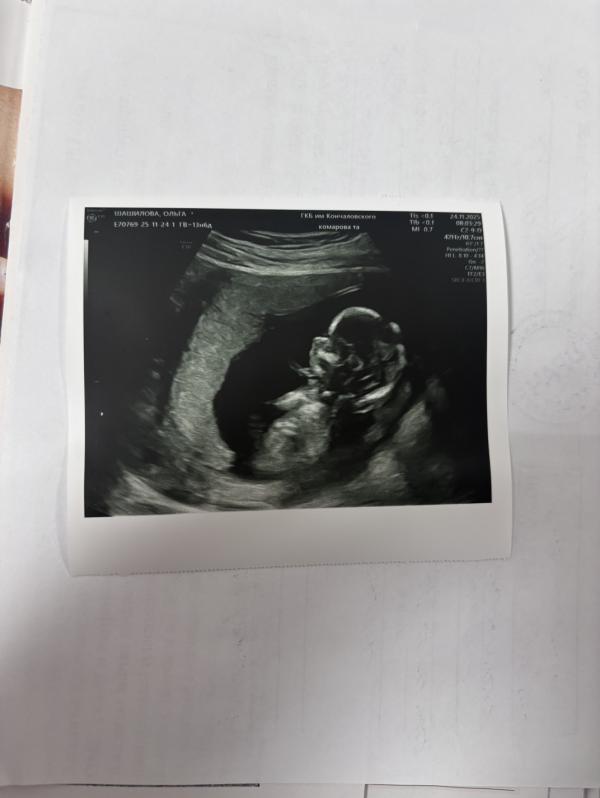

Получила в ЕМИАСе результаты первого скрининга. Высокий риск преэклампсии 😳 кто сталкивался, расскажите, что делали. Волнуюсь, а к врачу попаду только в понедельник. Но слава Богу, что все остальные риски низкие 🙏 а тут фото узи малыша 😍